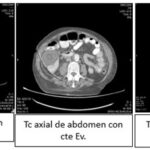

Se trabajó bajo un diseño no experimental, lo que significa que no hubo manipulación de variables, bajo un enfoque horizontal retrospectivo, descriptivo y observacional, donde se empleó la tomografía computada como método diagnóstico principal para el diagnóstico de lesiones quísticas renales. Se utilizó el tomógrafo PHILIPS ACCESS CT (Anexos 13, 14 y 15), emitiendo 16/32 cortes, realizado por médicos especialistas en diagnóstico por imágenes, siguiendo la clasificación Bosniak para categorizar cada uno de los 523 quistes estudiados y poder distinguir por medio del uso de contrastes si correspondían a quistes simples ubicados en la categoría I o a quistes complicados o malignos, los cuales se ubican en las categorías III y IV de Bosniak.

Cabe destacar que para la interpretación de resultados imagenológicos, descripción y posterior reporte de cada tomografía se utilizó el sistema de datos SYNAPSE, realizada por médicos especialistas en diagnóstico por imágenes con más de 20 años de experiencia basándose en la clasificación Bosniak para categorizar cada una de las lesiones quísticas.

Resultados según clasificación Bosniak

- Bosniak I: el 80% de los quistes (418 pacientes) fueron clasificados como Bosniak I, es decir, quistes simples hallados incidentalmente en tomografía computada (TC) y sin necesidad de seguimiento adicional. De estos, 268 pacientes eran de sexo masculino y 150 de sexo femenino (Anexos 17 y 18).

- Bosniak II: el 10% de los quistes (55 pacientes) fueron catalogados como Bosniak II, correspondientes a quistes benignos. Esta categoría incluyó a 36 pacientes de sexo masculino y 19 de sexo femenino (Anexos 19 y 20).